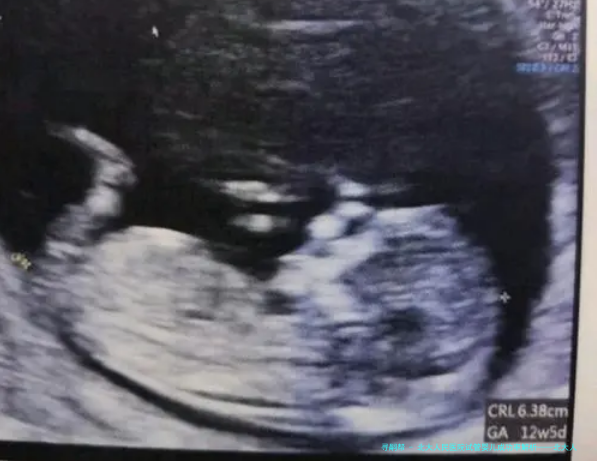

北大人民医院试管婴儿中心享有一支专业的医疗团队,采用国际先进的试管婴儿技术,为病人提供品质高的医疗服务。根据医院揭晓的数据,北小孩儿民医院试管婴儿成功率在业内处于领先水平。

北小孩儿民医院试管婴儿成功率受许多种因素影响,囊括病人岁数、不孕不育缘由、卵子质量、精子质量等。对在年轻时、卵巢机能优良的病人,成功率相应较高。此外,医院通过完善治疗方法、提高实验室技术水平等手段,不断提高试管婴儿成功率。